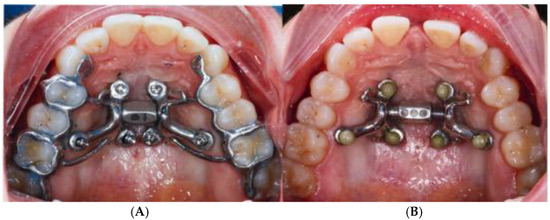

2.4. Case A: Blind Midpalatal Piezocorticotomy with MARPE Expansion

2.5. Case B: Guide-Assisted Midpalatal Piezocorticotomy